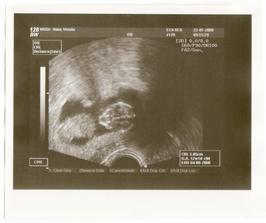

12+1...máme zase o 2 cm víc...hurá!!!